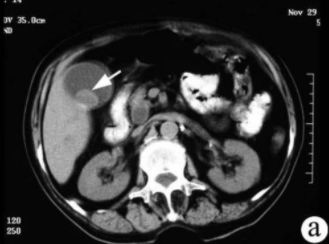

CT的密度分辨率高,更有利于胆结石的发现。胆石的CT表现与其化学成分密切相关,其CT值与胆固醇含量呈负相关,与胆红素和钙含量呈正相关。

CT表现主要有:高密度结石(均匀或不均匀);略高密度结石;等密度结石,与胆汁密度相等平扫不易区分;低密度结石;环状结石。